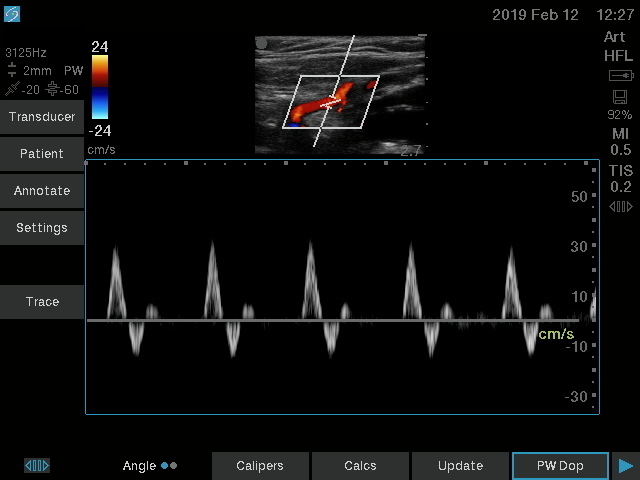

Vasküler Erişim için Sonosite SII-VA, hat yerleştirmeleri sırasında kullanım kolaylığı ve güvenilirliği nedeniyle klinisyenler için ideal bir araçtır. Basitleştirilmiş, dayanıklı ve uygun fiyatlı olan bu sistem, birincil bir amaç için yaratılmıştır: Ultrason rehberliğinin yardımıyla Merkezi hatlar, PICC’ler ve Periferik IV’ler gibi vasküler erişim prosedürlerinin başarı oranlarını iyileştirmenize yardımcı olmak.

Daha iyi görüş, daha derin anlayış. Sonosite, klinisyenlerin en zorlu ihtiyaçlarını karşılamak için yeni bir görüntü performansı standardını yeniden tanımlıyor.

| Doğrusal | 13-6 MHz | 6 cm | Arteriyel, Venöz |